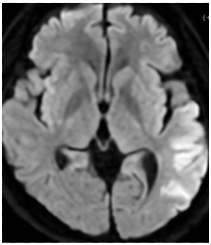

A 53-year-old man was admitted to our hospital with a diagnosis of cardioembolic stroke after the sudden onset of aphasia and conjugate deviation of the eyes. On admission, his blood pressure was 111/73 mmHg, and his heart rate was 111 beats per minute with an irregular rhythm. The respiratory rate was 20 breaths per minute, and oxygen saturation was within the normal range. Physical examination revealed no cardiac murmurs, with only mild bilateral leg edema noted.

Electrocardiogram showed atrial fibrillation with a heart rate of 116 bpm and no significant ST-segment changes. Chest radiography showed cardiomegaly. Laboratory analysis showed an elevated NT-proBNP of 6103pg/mL. Transthoracic echocardiography demonstrated an ejection fraction of 15%, left atrial diameter of 60mm, global wall motion abnormalities. Transesophageal echocardiography confirmed the presence of a thrombus in the LAA.

The patient had reduced left ventricular function, and tachycardia-induced cardiomyopathy was initially suspected. We therefore aimed for early restoration of sinus rhythm. Despite treatment with rivaroxaban, the patient developed a cardioembolic stroke, and a thrombus persisted in the LAA. Anticoagulation was switched to warfarin. During stroke rehabilitation and optimization of cardioprotective therapy, we monitored the thrombus for resolution, but it remained unchanged. Because an LAA occlusion device cannot be used in the presence of an existing thrombus, and thoracoscopic LAA resection is feasible when the thrombus does not extend to the LAA base, we decided to perform thoracoscopic LAA resection on hospital day 70. Intraoperative transesophageal echocardiography confirmed the absence of thrombus at the LAA base before resection. A thrombus was found within resected LAA specimen. However, postoperative computed tomography on hospital day 79 revealed hypoattenuated thickening (HAT) at the resection stump, suggestive of thrombus formation. Transesophageal echocardiography confirmed this finding. After intensifying warfarin management, the thrombus resolved approximately 20 days later. Catheter ablation was subsequently performed on hospital day 115, and the patient has since maintained sinus rhythm.